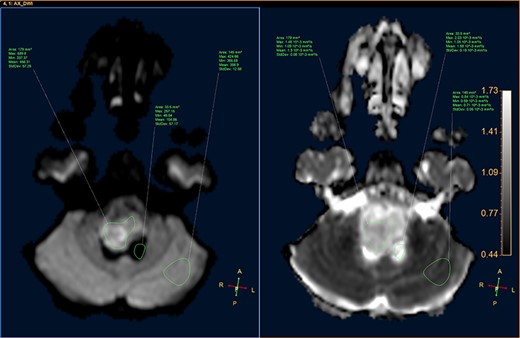

DWI image and ADC map, showing the CSF, lesion and normal-appearing parenchyma.

A 3-year-old male, who suffered from a sudden, tonic–clonic seizure, followed by a short period of unconsciousness, was instantly transported to Children’s Hospital 2. The patient’s medical history was normal. No neurological deficits were detected during the clinical assessment, and laboratory tests and electroencephalography were within acceptable ranges. The clinician performed a brain magnetic resonance imaging (MRI) scan, with contrast agent. No lesions were recognized in the supratentorial structures. A clear boundary cystic mass (27 × 25 × 26 mm3) was located in the medulla oblongata, without perilesional vasogenic edema. Hydrocephalus was not observed. The signal intensity of the mass was low on the sagittal T1-weighted image (Fig. 1) and high on the axial T2-weighted image (Fig. 2). On coronal fluid-attenuated inversion recovery imaging, the mass was isointense relative to the parenchyma, but the intensity was higher than that of cerebrospinal fluid (CSF, Fig. 3). On susceptibility-weighted imaging, no indicators of hemorrhage or ossification were observed within the mass. The mass was partially hyperintense on diffusion-weighted imaging (DWI) and slightly hypointense on the apparent diffusion coefficient (ADC) map. The mean ADC values of the parenchyma, mass and CSF were 0.71, 1.3 and 1.59 × 10−3 mm2/s, respectively (Fig. 4). On T1-weighted imaging, with contrast enhancement, the thin wall of the mass was very slightly enhanced, and we observed a tiny nodule inside the mass that was strongly enhanced (Fig. 5). With a provisional diagnosis of pilocytic astrocytoma, the patient underwent surgery to completely eradicate the tumor. Eventually, the histopathological result revealed a typical EC (Fig. 6). The postoperative period was uneventful, and the patient was discharged after 2 weeks.

Histopathologically, the ECs are filled with protein, keratin and cholesterol. The cyst wall is typically covered with stratified, squamous epithelia, with the outward backing of collagen [3–8]. The appearance on MRI is heavily dependent on the chemical architecture of these intracystic components. The hypointensity observed on T1-weighted images is associated with the crystalline cholesterol pattern, whereas the hyperintensity on T2-weighted images is induced by the keratinaceous element. Occasionally, ECs appear hyperintense on T1-weighted images and hypointense on T2-weighted images, and these are referred to as white ECs [8, 9]. This specific appearance is caused by unusually high proteinaceous concentrations in the cyst. Typically, ECs do not absorb contrast agent vividly. Approximately 35% of ECs are estimated to enhance slightly and peripherally [9]. DWI is the most useful weapon that can be deployed to recognize ECs. When contrasted with the CSF, because of the superior keratinaceous and proteinaceous concentrations and the relatively little aqueous content, ECs generally appear considerably hyperintense on DWI and hypointense on ADC [9, 10].

Although some recommended imaging characteristics exist for ECs, these characteristics are not always persistent or specific [8–10]. Especially in cases of intraparenchymal ECs, provisional diagnosis can be very difficult due to similarities between EC characteristics and those of other brain neoplasms, including glioma [3–10]. In our case, we identified a medulla oblongata mass in a 3-year-old patient, with a lesion ADC of 1.3 × 10−3 mm2/s, and the identification of an enhanced mural nodule in a cystic lesion resulted in the misdiagnosis of pilocytic astrocytoma, a very common, benign, posterior fossa tumor found in children. According to Kannan et al. [10], unlike extra-axial ECs, intraparenchymal ECs do not often exhibit distinctly limited diffusivity.